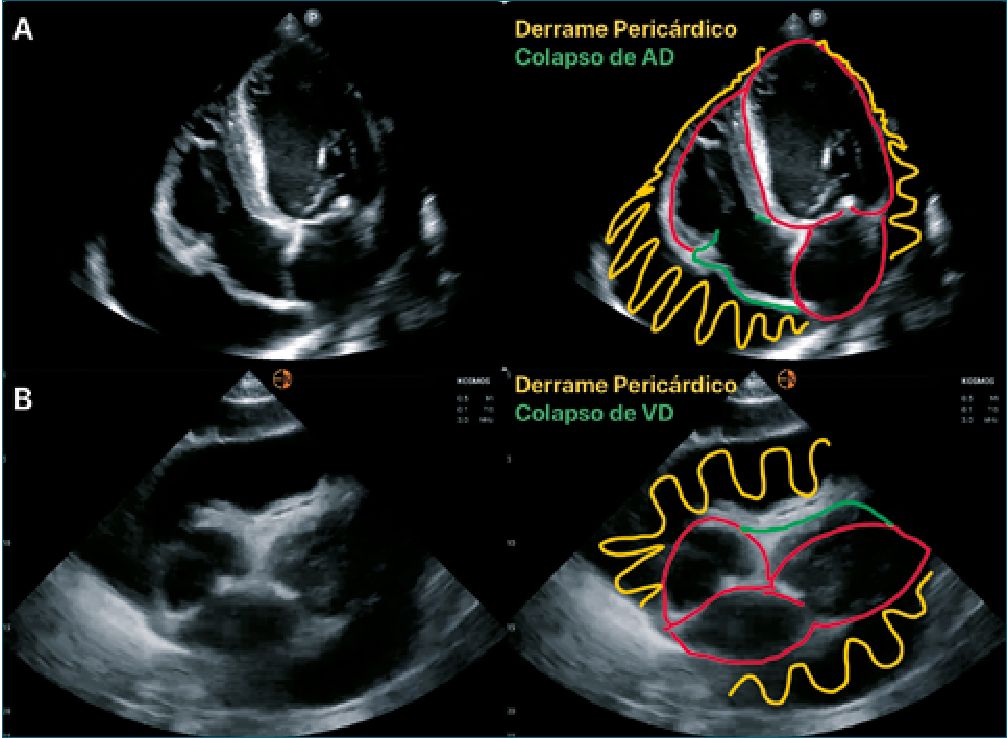

En el taponamiento cardíaco hay diferentes marcadores como el colapso diastólico del ventrículo derecho que tiene una especificidad alta (75%-90%) y una sensibilidad relativamente baja (48%-60%), el colapso sistólico de la aurícula derecha es el signo más temprano con una especificidad variable (33%- 100%), mientras que la sensibilidad es alta y puede variar en la etapa inicial (50%); en la etapa de progresión (100%), la vena cava inferior pletórica con variación respiratoria mínima tiene una sensibilidad muy alta (95%-97%) y una especificidad más baja (40%); el pulso paradójico tiene una sensibilidad del 82% [12] (Figura 2).

Figura 2. Datos ecográficos de taponamiento cardíaco.